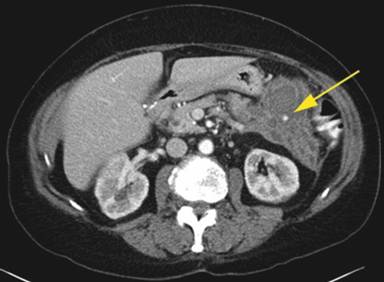

A 64-year-old Caucasian female was referred to our facility for further management of hemorrhagic pancreatitis. The patient had previously presented to an outside hospital with acute onset of severe sharp mid-abdominal pain, back pain, and nausea. She had no prior history of pancreatitis or alcohol use and had a prior cholecystectomy. Initial laboratory tests revealed a normal lipase, calcium, and triglyceride level. She had a history of hypertension, emphysema, depression, and spinal stenosis. She also had breast cancer 13 years prior, which had been treated by lumpectomy, chemotherapy, and radiation. Computed tomography (CT) scan displayed a heterogeneous fluid collection 14.3x11.2x10.0 cm and was interpreted as hemorrhagic pancreatitis involving the body and tail of the pancreas. Before admission to our hospital, she had required intensive care unit support including intravenous antibiotics and a transfusion of one unit packed red blood cells. She was started on total parenteral nutrition and took nothing by mouth. After seven days of support, she continued to have abdominal pain and was referred to our institution. Upon arrival to our facility, the patient was hemodynamically stable and afebrile. A repeat CT of the abdomen with intravenous contrast was performed at our facility 17 days after initial outside presentation (Figure 1), and it demonstrated a heterogeneous fluid collection 9.1x5.8 cm in the anterior pararenal space inferior to pancreatic tail, which likely represented a hematoma. There was also a 6 mm small pseudoaneurysm within the central portion of the fluid collection. There was no evidence of pancreatitis. An angiogram was subsequently performed and demonstrated dilatations and strictures with multiple pseudoaneurysms in the branches of the superior mesenteric artery, inferior mesenteric artery, ileal colic artery, and hepatic arteries, with one being adjacent to the pancreas (Figures 2 and 3). An attempt to embolize the pseudoaneurysm within the hematoma was unsuccessful due to tortuous mesenteric arteries. Other laboratory data obtained included C-reactive protein at 36 mg/L (reference range: 0-8.0 mg/L) and erythrocyte sedimentation rate of 72 mm/h (reference range: 0-29 mm/h). The workup for vasculitis included anti-nuclear antibodies, anti-citrullinated protein antibodies, rheumatoid factor, anti-double stranded DNA antibodies, and complement levels, all of which were within reference limits. Proteinase antibodies and myeloperoxidase antibodies were also negative. Her leukocyte count was not elevated and blood cultures were negative for growth. There was no history of congenital vascular disorders. She had no skin lesions and no renal or neurological abnormalities. A diagnosis of segmental arterial mediolysis was given based on exclusion and imaging. The patient was monitored in the hospital setting for 6 days after transfer and remained hemodynamically stable. Once abdominal pain resolved and the patient was tolerating a regular diet, she was discharged with close follow-up. A CT angiogram conducted four (Figure 4) and eleven months later (Figure 5) revealed resolution of mesenteric pseudoaneurysms and peripancreatic hematoma.

Figure 1. CT abdomen with contrast revealing heterogeneous peripancreatic fluid collection with pseudoaneurysm. |